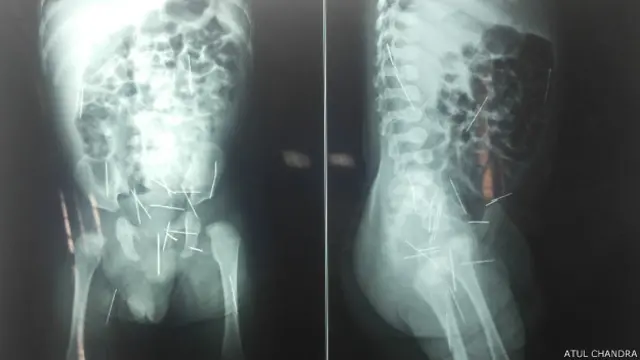

चार माह के बच्चे के शरीर के अंदर 25 सुइयां!

चार माह के एक बच्चे के शरीर के अंदर 25 सुइयां पाई गई हैं. ये सुइयां उसके पैर, हाथ, पेट यहां तक रेक्टम के रास्ते किसी ने बेरहमी से डाली हैं. ये काम किसने किया ये अभी पता नहीं चला है.

सोमवार को लखनऊ के किंग जॉर्ज मेडिकल यूनिवर्सिटी के बाल शल्य चिकित्सा विभाग के अध्यक्ष प्रोफेसर एस एन कुरील ने बच्चे का ढाई घंटे ऑपरेशन कर तीन सूइयां निकाली.

डॉक्टर कुरील ने बताया कि ये तीनों सूइयां बच्चे के पेशाब के रास्ते को बंद किए हुए थीं और वहां से खून आ रहा था और अंदर पस पड़ गया था.

डॉक्टर का कहना है कि ये सूइयां प्लास्टिक की सिरिंज से तोड़ कर बच्चे के बदन में डाली गई हैं.

डॉक्टर कुरील का कहना है, "अपनी तरह का ये पहला केस है जब किसी बच्चे के बदन में एक साथ इतनी बाहरी चीज़ें डाली गई हों. एक-दो सुइयों के उदाहरण तो हैं लेकिन 25-26 सुइयां, इसका ज़िक्र हम लोगों को नहीं मिला है.

इसके बाद शिवेंद्र और सत्याक्षी बच्चे को लेकर ज़िला अस्पताल पहुंचे जहां एक्सरे में उसके बदन के अलग-अलग हिस्सों में सुइयां पड़ी हुई थीं.